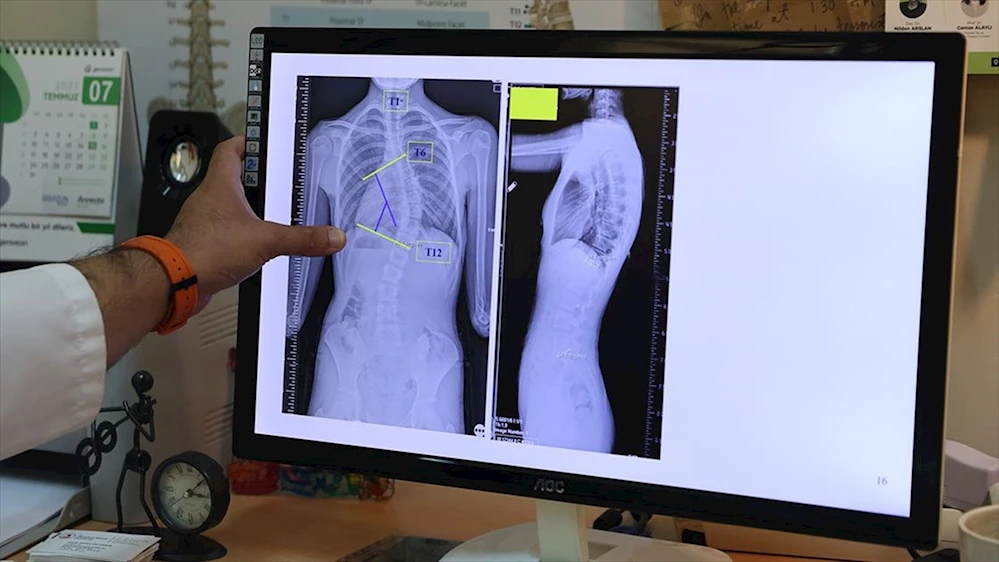

SAMSUN (AA) - Doç. Dr. Coşkun, AA muhabirine, omurganın ön ve arka planında 10 dereceden fazla olan eğriliği skolyoz hastalığı olarak kabul ettiklerini belirtti.

Skolyozun duruş bozukluğundan ayırt edilmesi gerektiğini vurgulayan Coşkun, duruş bozukluğunun basit egzersizlerle düzelebileceğini, skolyozda ise omurga yapısında bir deformasyondan söz ettiklerini anlattı.

Coşkun, skolyozun genellikle 10-19 yaş aralığında görüldüğüne işaret ederek, 'Skolyoz, nedeni bilinmeyen bir hastalıktır. Ergenlik, adölesan idiopatik skolyozun en sık görülen yaş grubunu oluşturmakta. Şikayetler genelde omuzların bir tarafında yükseklik farkı olması, bir omuzun daha yukarıda yerleşmesi. Ayrıca hasta öne doğru eğildiğinde, hastada bir tarafında sırtında bir yükseklik, bir kamburluk bulgusu olması. Bu yükseltinin bir tarafta belirginleşme, diğer tarafta silinme, skolyozun ana bulgularındandır.' dedi.

'Skolyoz hastalığında tedavilerden biri gözlem tedavisidir. Gözlem skolyozda bir tedavidir. Biz gerçekten de 0 ila 20 derece arasındaki eğriliklere pek bir şey yapmayız. Bu çocukların gelişimini takip ederiz ve erişkin yaşa geldiğinde de bu tedaviyi sonlandırırız. Artık bu çocukların bir riski, hastalığın ilerlemesi açısından yoktur. 20 ila 40 derece arasında ise ya da 45 dereceye kadar biz çocuğun yaşı eğer uygunsa korse tedavisi uygularız. Korse tedavisi için çocuğun büyümesinin devam etmesi lazım. Kemik yaşı tamamlan, büyümesi tamamlanmış bir çocukta korse tedavisinin yeri yoktur. 45 dereceyi aşan eğriliklerde ise eğriliğin her sene ilerleyeceğini öngörerek cerrahi tedavi uygulamaktayız.'

Skolyozun özellikle kız çocuklarında daha sık görüldüğünün altını çizen Coşkun, ergenlik öncesi çekilecek bir omurga röntgeninin tedavide daha iyi yol alınmasını sağlayacağına işaret ederek, 'Kız çocuklarında doğumsal kalça çıkığında olduğu gibi skolyoz yönünden tedbirli olmakta fayda var. Özellikle adet öncesi dönemde kızların en azından bir omurga röntgeninin çekilmesi, yine erkeklerde de ergenlik öncesi dönemde bir kez omurga röntgeninin çekilmesi olası bir skolyoz hastalığının tedavisine erken başlamak adına önemli. Çünkü tedaviye ne kadar erken başlarsak o kadar iyi sonuç alma ihtimalimiz yüksek.' ifadelerini kullandı.